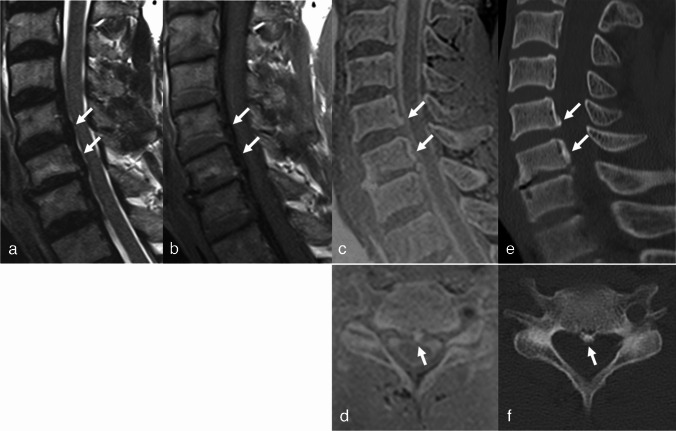

目的:比较三维快速低角度镜头(FLASH)与常规MRI序列对OPLL的诊断价值。材料和方法:本回顾性研究包括106例颈椎MRI和CT检查。OPLL组和对照组分别入组39例和67例患者。比较常规MRI使用涡轮自旋回波(TSE)和常规MRI加3D FLASH检测OPLL的诊断性能和读取器置信度。还计算了观察员间的一致意见。根据检测OPLL所需的序列,在OPLL组中定义了三个亚组(TSE组:仅通过检查TSE诊断为OPLL的病例;3D FLASH组:同时通过TSE和3D FLASH进行诊断的病例;无组:未经MRI诊断的病例)。比较各亚组间上pll的厚度。结果:常规MRI加入3D FLASH后,两种读卡器的诊断性能均有提高,其中读卡器2的差异有统计学意义(p = 0.006)。结论:3D FLASH与常规T1、t2加权成像相结合可有效检测OPLL。

Materials and methods: This retrospective study included 106 patients who underwent cervical spine MRI and CT. Thirty-nine and 67 patients were enrolled in the OPLL and control groups, respectively. Diagnostic performance and reader confidence for detecting OPLL were compared between conventional MRI using turbo spin echo (TSE) and conventional MRI plus 3D FLASH. Interobserver agreement was also calculated. Three subgroups were defined within the OPLL group according to the sequences required for detecting OPLL (TSE group: cases that were diagnosed as OPLL by reviewing only TSE; 3D FLASH group: cases that were diagnosed by reviewing both TSE and 3D FLASH; none group: cases that were not diagnosed on MRI). The thickness of the OPLL was compared between the subgroups.

Results: The diagnostic performance of both readers improved when 3D FLASH was added to conventional MRI, and the difference was statistically significant for reader 2 (p = 0.006). After adding 3D FLASH, reader confidence significantly increased (p < 0.001), and interobserver agreement improved from good to excellent. The three subgroups exhibited significantly different OPLL thicknesses (p = 0.008), with the thickest in the TSE group (4.5 mm), followed by the 3D FLASH (3.4 mm) and None groups (2.4 mm).

Conclusion: 3D FLASH can be helpful for detecting OPLL when combined with conventional T1- and T2-weighted imaging.